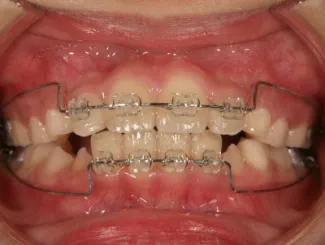

ブラケット

治療中④中2:マルチブラケット法へ移行:上下正中を合わせたい

*マルチブラケット法